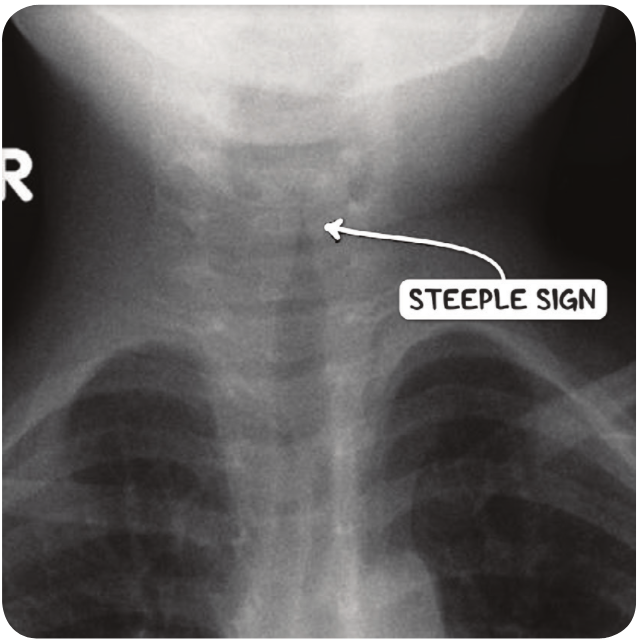

הדמייה- לא ספציפי ולא רגיש Steeple sign= צריח בקנה

מהו הממצא

A

Steeple sign

היצרות של הטרכיאה , קנה צריח

מאפיין Croup